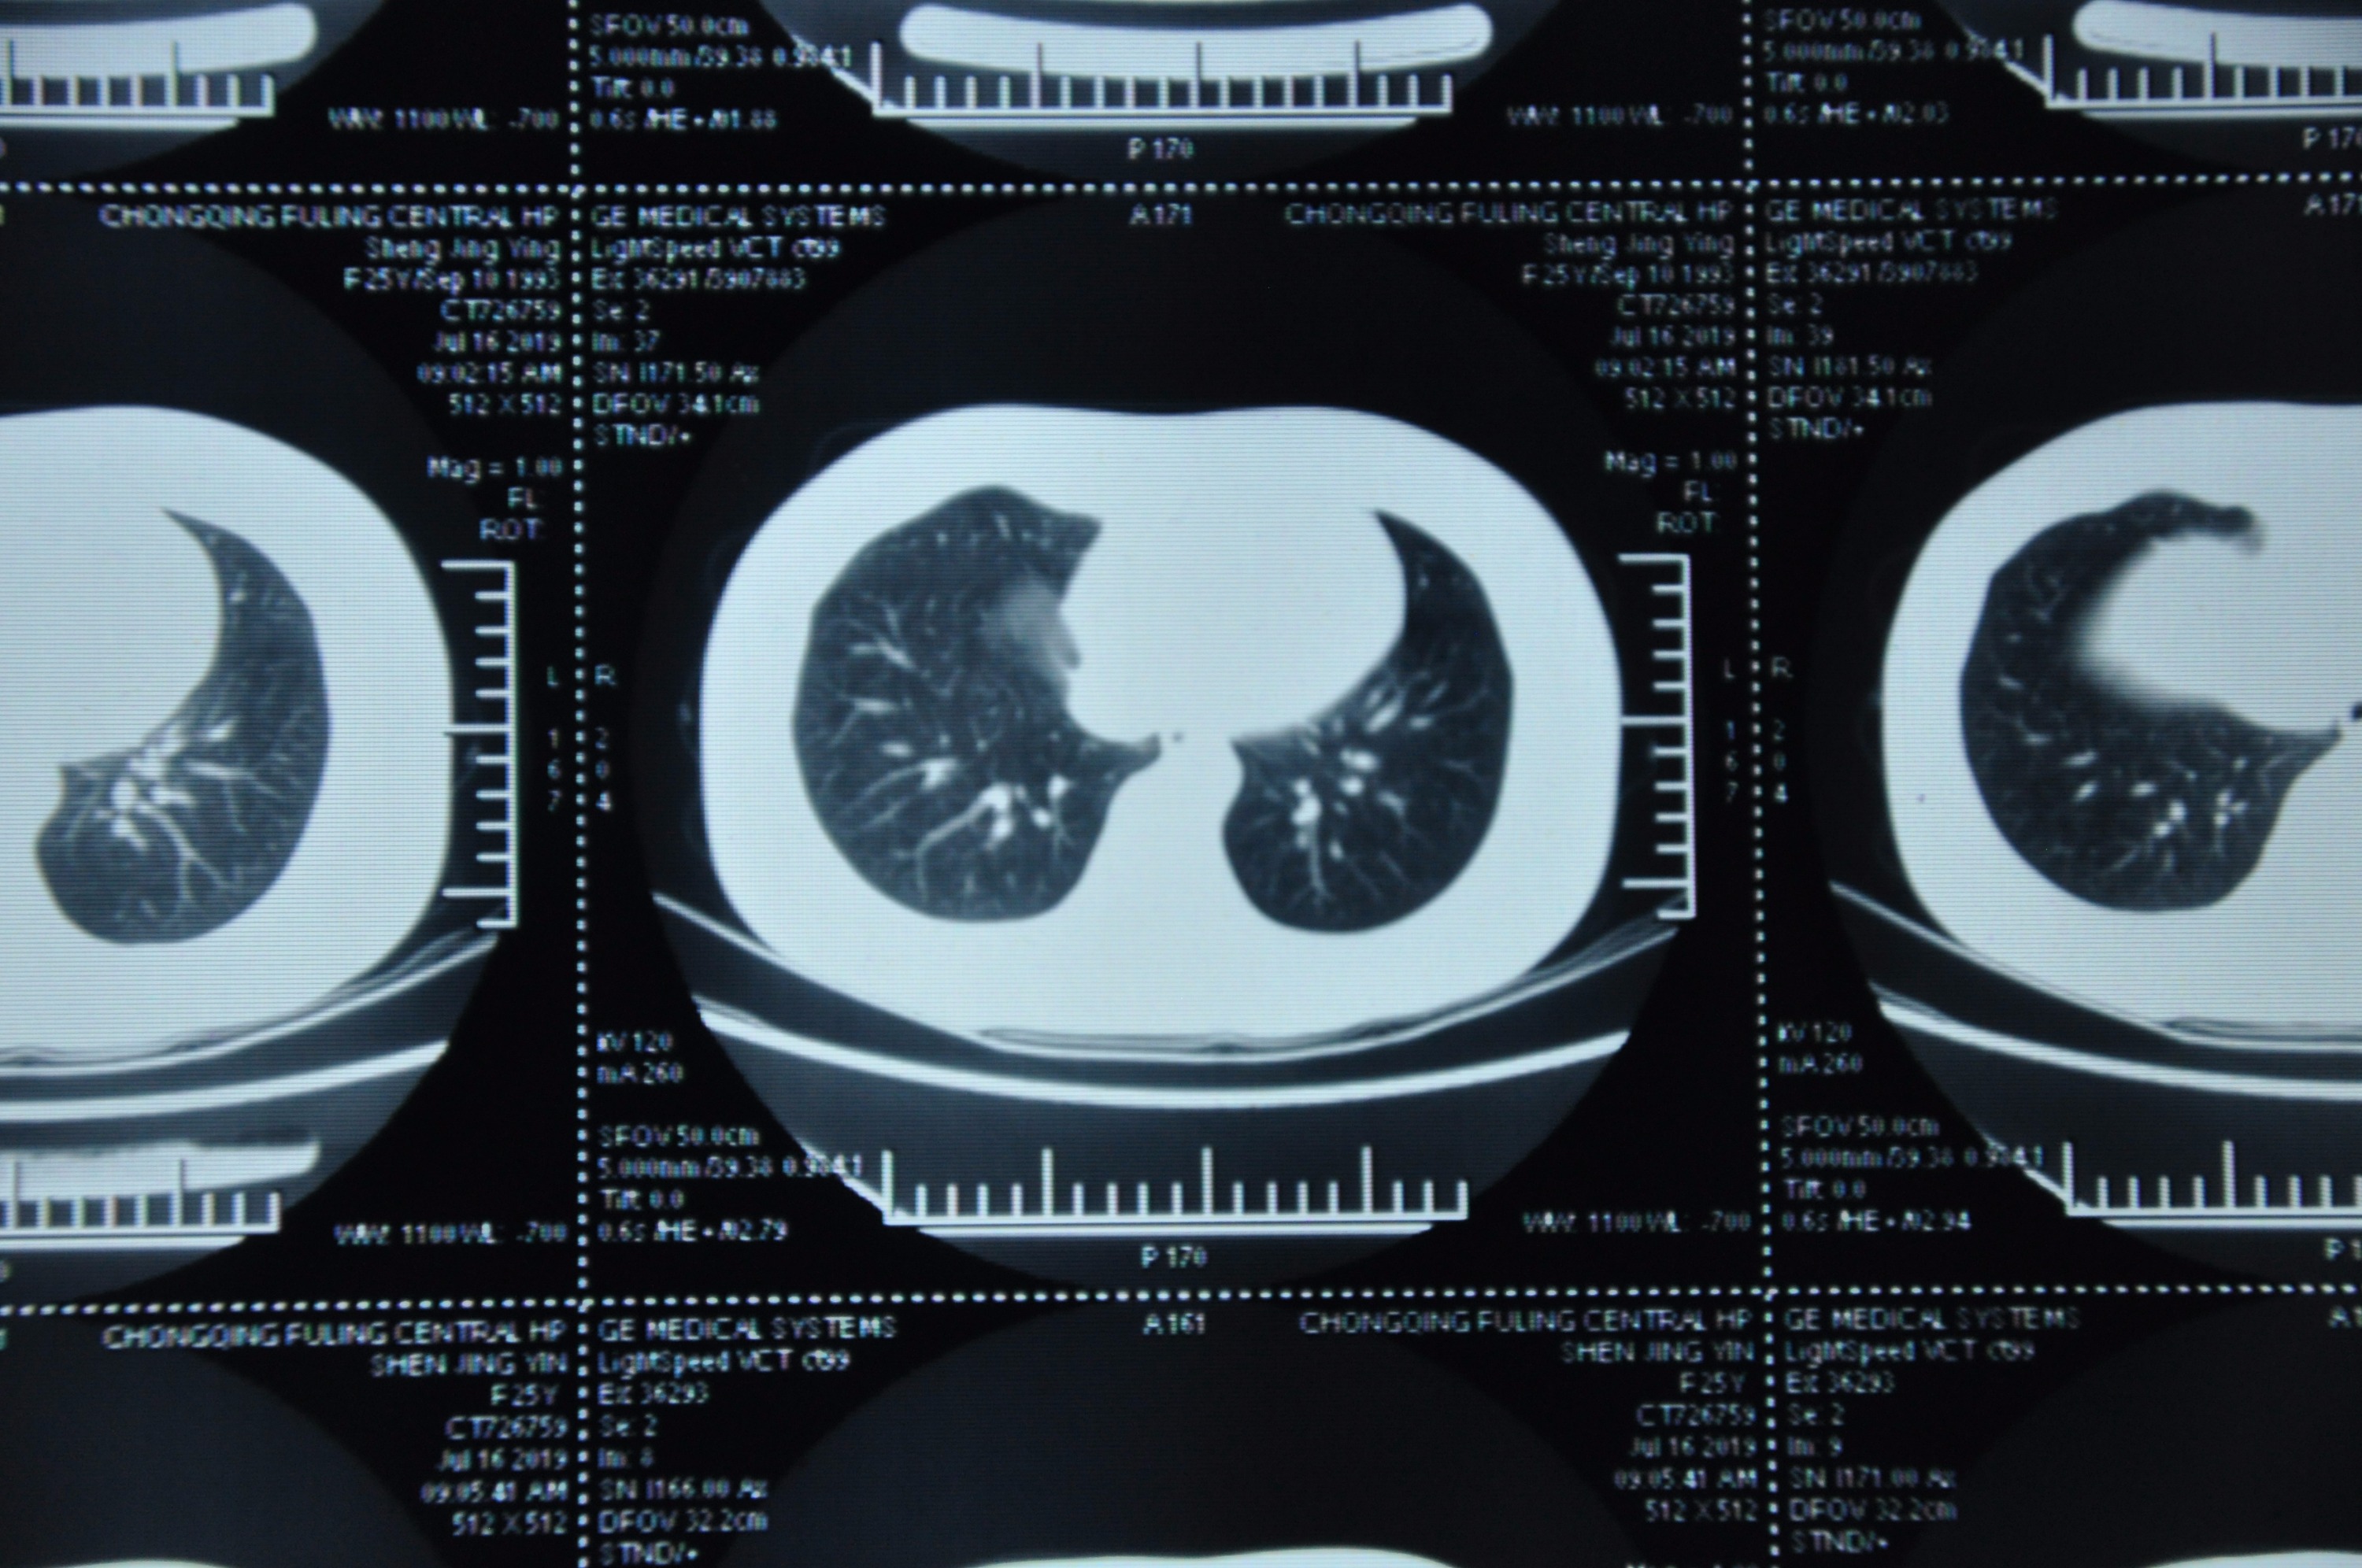

参加gwy入职体检检出来肺结节,请戴主任帮我看一下,是不是我得过结核,我现在有没有结核?还有现在能判断良性恶性吗?怕体检被刷下来

不知道能不能看得清楚